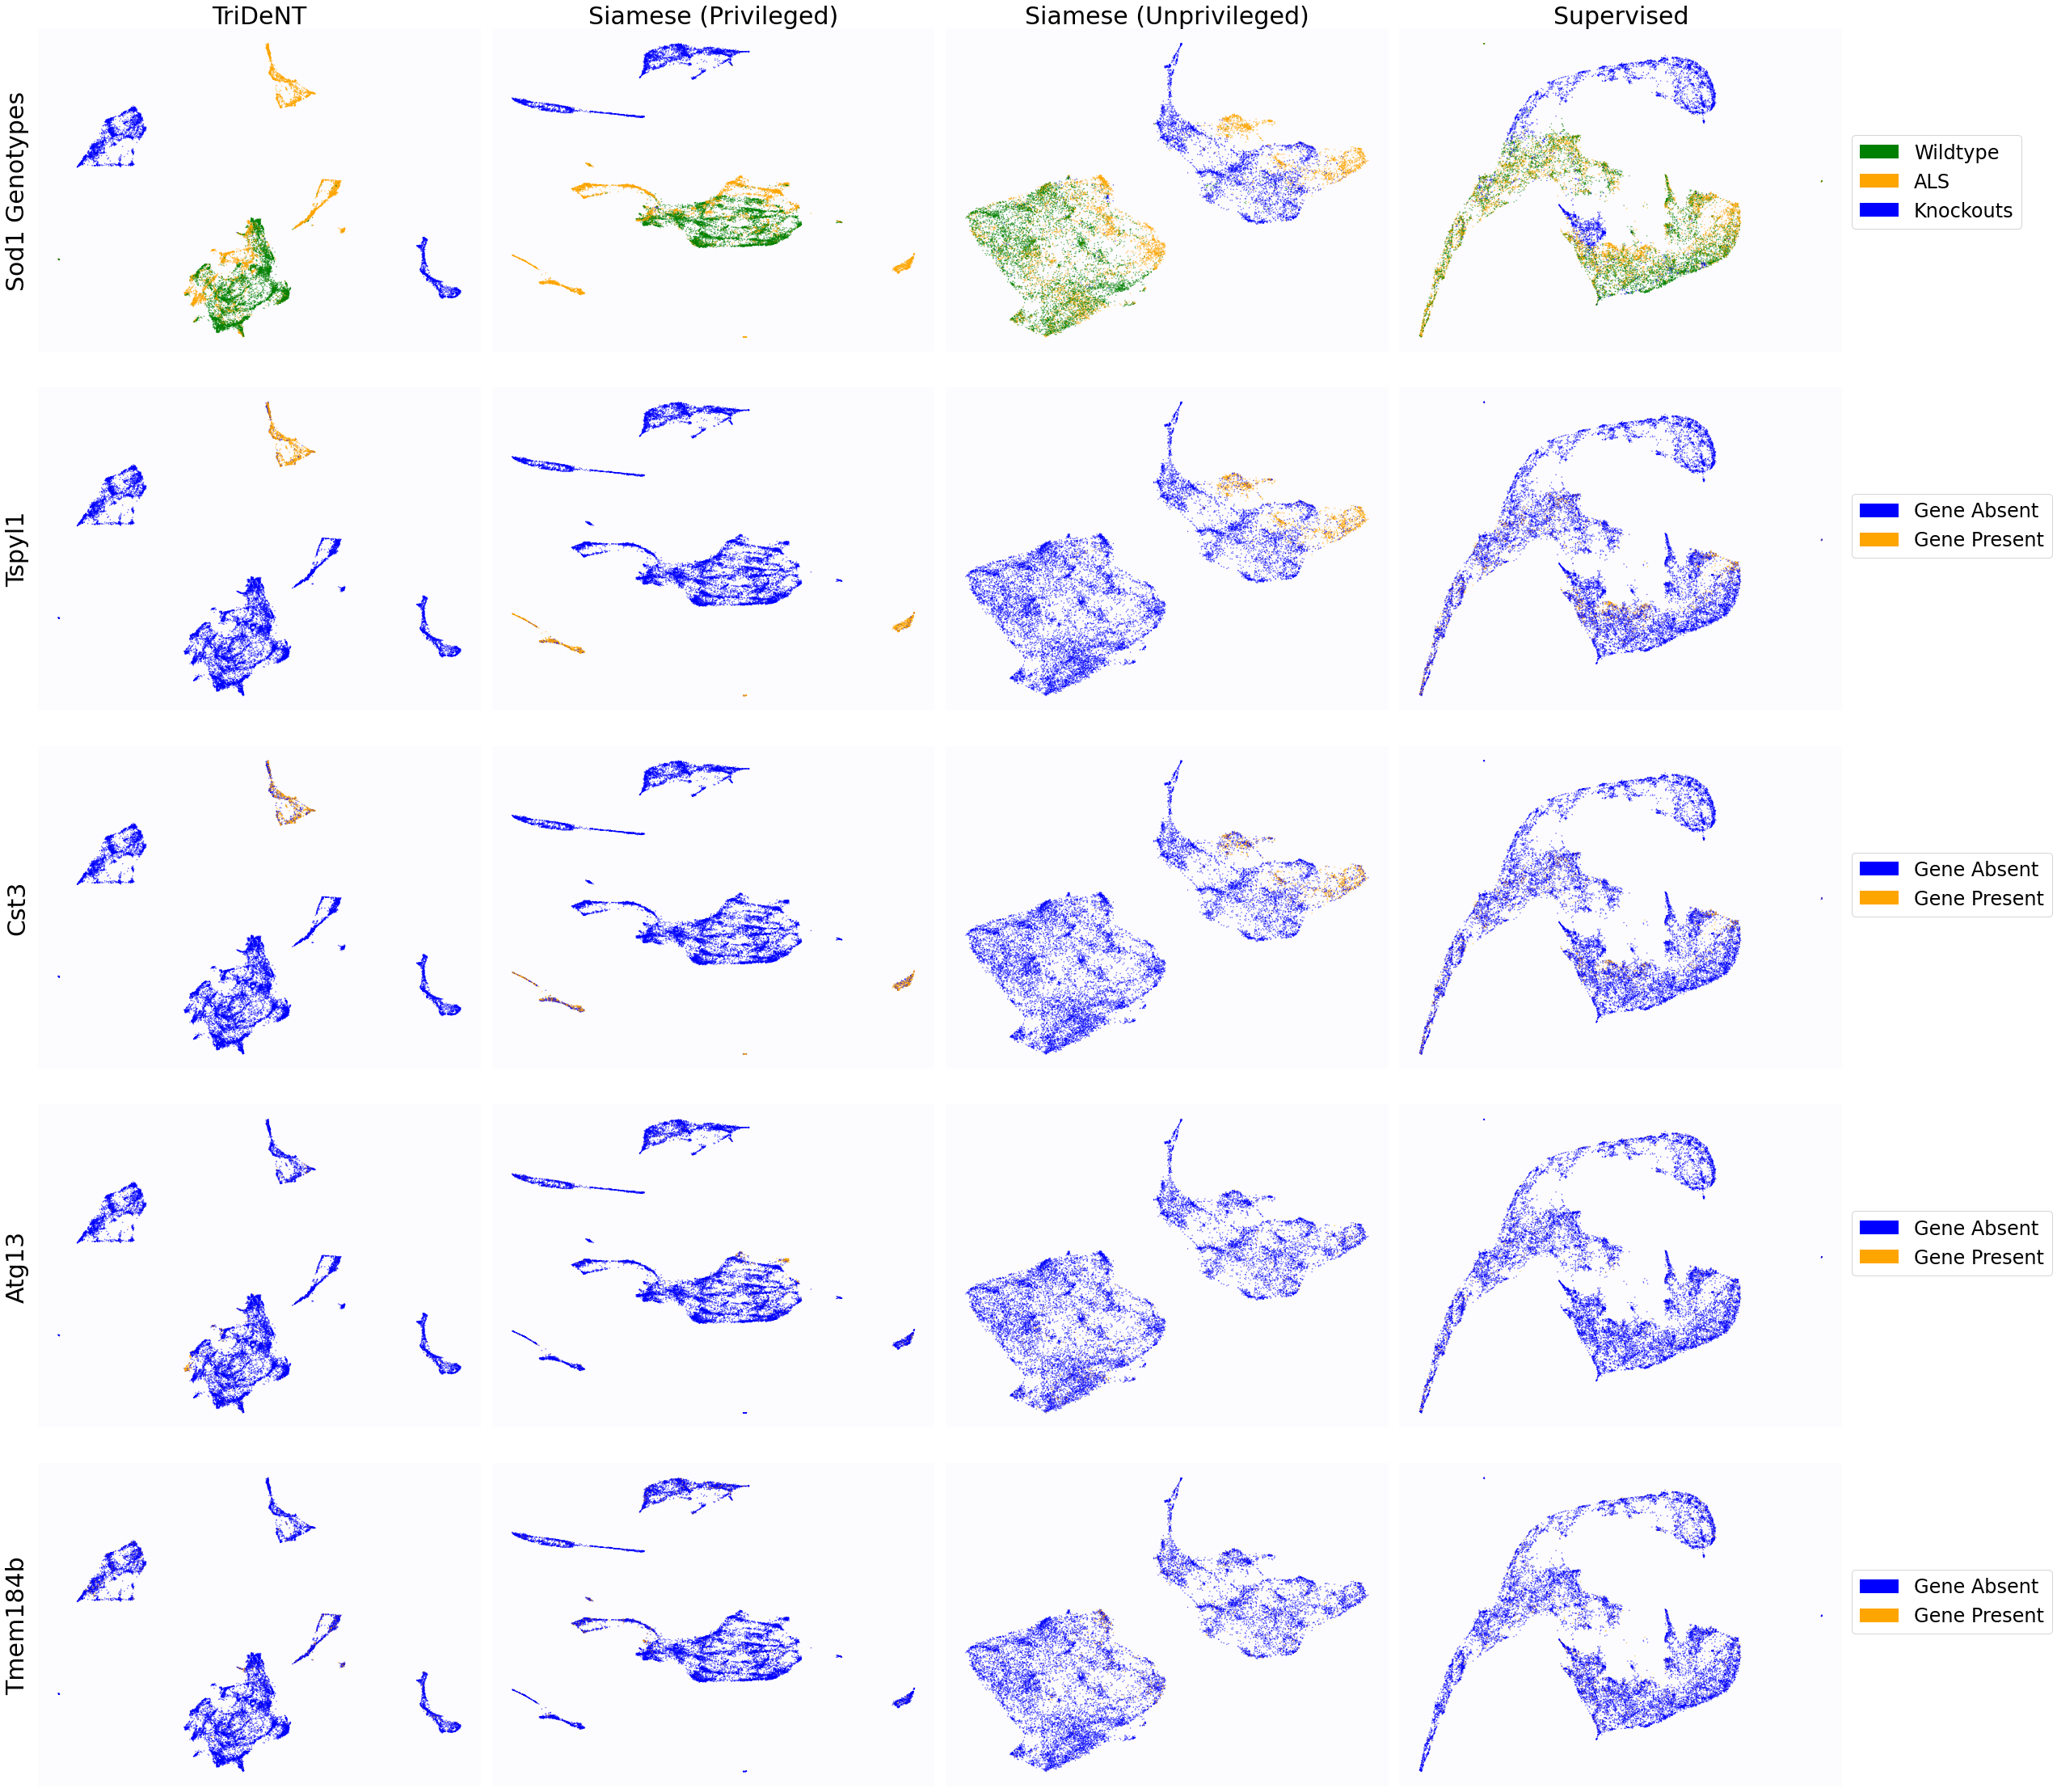

To assess the level of information shared between the transcriptomic results and the representations of the H&E patches, we investigate the cross-correlation between elements of the representations and the gene counts for each matching patch. We calculate the cross-correlation across the validation set between each element in the representations and the count for each gene, and for each gene take the correlation of the corresponding element with the maximum correlation or minimum anti-correlation, whichever has the greater absolute value. This maximum/minimum is chosen because the vast majority of elements will not correlate with any given gene, and the absolute value is taken because the sign of the element is arbitrary, so correlation and anti-correlation are equivalent. We use the absolute value of the correlation for the element selected for each gene, and use these to generate the histograms in Figure 3(a). It is clear that privileged training obtains representations which are far more correlated to the gene counts than unprivileged training, with minimal differences in the correlations between TriDeNT ♆ and Siamese approaches. This implies that the models have learned equivalently informative representations about the coarse-grained features of the genes. Figure 3(c) demonstrates that the correlation strength is significantly greater for TriDeNT ♆ compared to an unprivileged Siamese model, and Figures S3 and S4 show the relationships between the gene correlations of representations from TriDeNT ♆, Siamese methods, and supervised learning. Figures S5 and S6 show the geneset enrichment for each method, demonstrating that TriDeNT ♆ captures more meaninful interrelationships that are more informative about the relationship between tissue morphology and gene expression than unsupervised Siamese models. This is especially important for scientific discovery, as these analyses are used to generate hypotheses for further research. Figure S7 shows UMAP projections of the representation space coloured by genotype and gene, to illustrate that TriDeNT ♆ identifies distinct morphological clusters which are not found by unprivileged Siamese models. Figure 3(a) also shows that the findings are robust to human and mouse datasets, indicating the generality of the method.

To further analyse the learned representations, we produce UMAP projections of the latent space labelled with the tissue types for the NCT tissue type classification task, as shown for CD3CD20 and SMA in Figure 4(a), and for all SegPath stains in Figures S8 and S9. These figures make the reasons for the varying performance of the privileged Siamese model more apparent. For stains with better performing privileged Siamese models, such as SMA, the UMAPs are very similar between Siamese methods and TriDeNT, with well-differentiated tissue type clusters. In those with worse performance, such as ERG, the tissue types are poorly differentiated, often with only adipose and background forming distinct clusters from the other classes. On closer inspection, it is notable in these projections that TriDeNT ♆ produces more well-defined and separated clusters in general than Siamese networks. This is further evidenced in Figure S7, where TriDeNT ♆ is shown to identify clusters with overexpression of a given gene significantly more effectively than an unprivileged Siamese model.